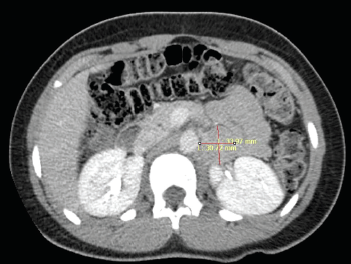

Jimisha Patel, MD; Kieran Leong, DO; Erin Conlin, MD; Eileen Baez-Irizarry, MD; Randall Craver, MD; Caroline Straatmann, MD; Michael Marble, MD; Alfonso Vargas, MD; Kenneth Ward, MD; Kathryn Beatty, MD

A 12-year-old girl with no significant past medical history presented with a 1-week history of chest pain, which she described as tightening with hyperventilation.